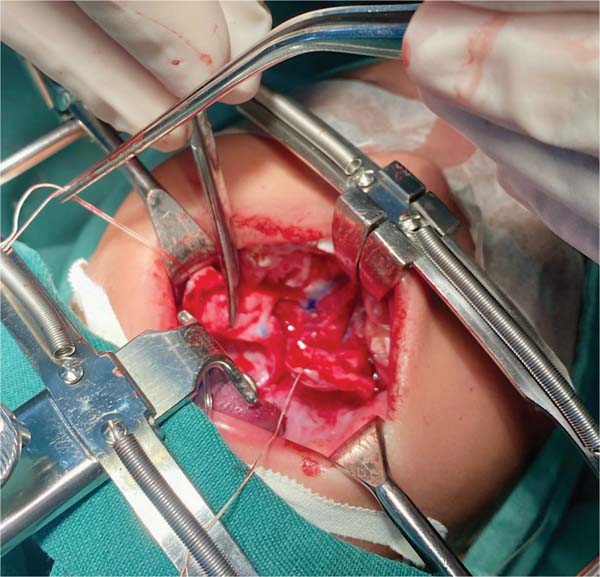

The new surgical tactic was designed to reduce suture tension in Pittsburgh’s zone III, where 50% of fistulas occur. This zone is a transitional area between the hard and soft palates, with thin tissues usually sutured in two planes, one in the nasal mucosa and the other in the oral mucosa. The proposed method introduces a third suture plane in the periosteum, a tissue more resistant to traction, with one or two U-shaped Vicryl-4.0 sutures (►Figs. 1–3).

The palatoplasty was performed under general anesthesia using the two-flap mucoperiosteal technique with intravelar veloplasty, following the principles of Sommerland41 and using lateral relaxing incisions. We applied sutures to the nasal mucosa and muscles, introducing a third suture plane in the transition zone, that is, using one to two U-shaped sutures in the periosteal plane in the distal portion of the mucoperiosteal flap. Then, we closed the oral mucosa and placed hemostatic material in the bloody areas. The patients received a liquid diet for 7 days and had no hand or arm movement restrictions.